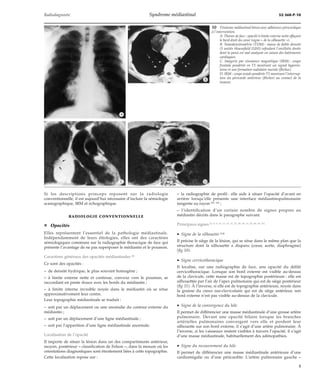

13 Signe thoracoabdominal (ou signe de l’« iceberg ») (cli-chés

dus à l’obligeance du Professeur Diard).

A. Ganglioneurome intrathoracique. L’extrémité infé-rieure

du contour externe de l’opacité rejoint le rachis

(flèches). Ceci traduit son origine supradiaphragmati-que.

B. Neuroblastome thoracoabdominal. L’extrémité infé-rieure

du contour externe de l’opacité s’écarte du rachis

(têtes de flèches). Cet aspect signe sa topographie thora-coabdominale.

· Signe de l’« iceberg » ou signe thoracoabdominal

Une masse médiastinale inférieure est thoracoabdominale si son

contour externe croise le diaphragme en s’écartant du rachis. En

revanche, si son contour inféroexterne rejoint le rachis elle est sus-diaphragmatique

(fig 13).